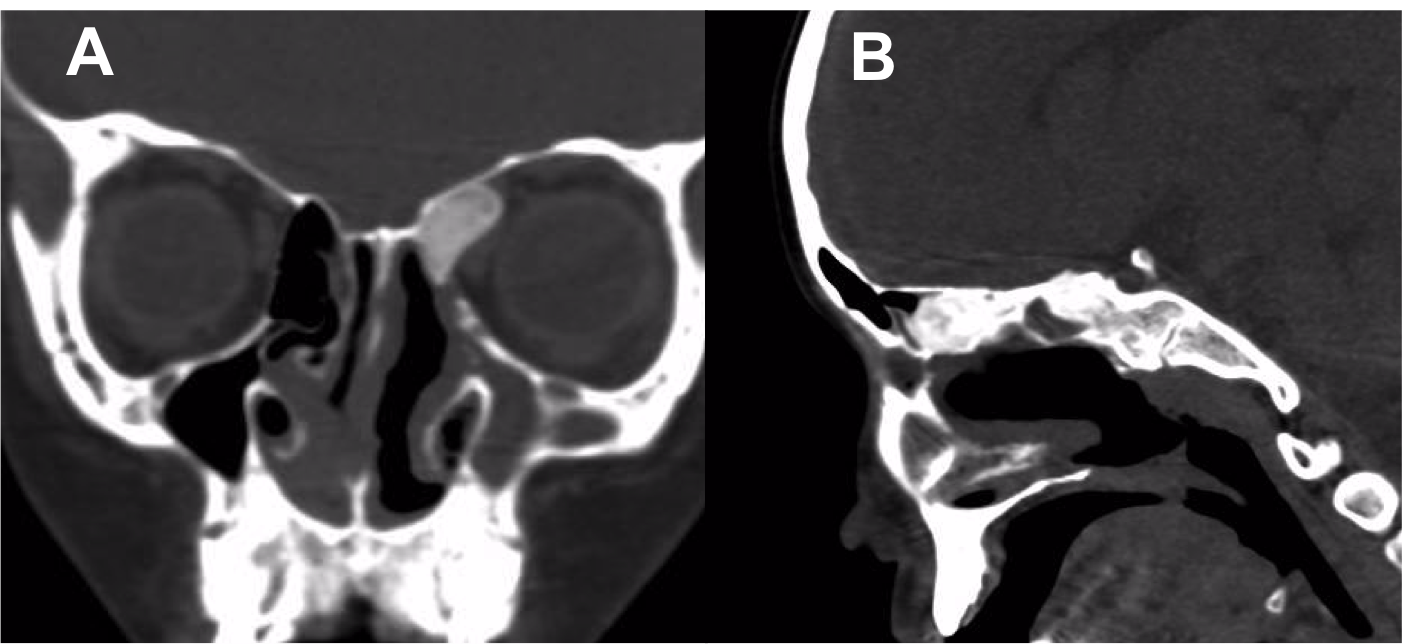

Introducción: La cirugía endoscópica endonasal se ha convertido en una herramienta fundamental para el manejo de patologías que comprometen la base de cráneo. En casos bien seleccionados, estas técnicas permiten resecciones quirúrgicas con una menor morbilidad sin comprometer los principios oncológicos de resección. Con el desarrollo de instrumental especializado, nuevas tecnologías y la experiencia de los cirujanos, la cirugía endoscópica endonasal se usa cada vez más en cirugía de base de cráneo en niños.

Resultados: Fueron intervenidos 8 pacientes entre los 2 y 14 años, con una edad promedio de nueve años y un seguimiento promedio de 16 meses. En el 75% se hizo una resección total del tumor. Un paciente requirió una reintervención y un paciente fue sometido a radiocirugía post-operatoria. 1 paciente falleció a pesar de múltiples intervenciones, quimioterapia y radioterapia.

Conclusión: La cirugía endoscópica endonasal para tumores de base de cráneo puede ser utilizada de forma segura en los pacientes pediátricos, es una técnica que en casos bien seleccionados pueden ofrecer excelentes resultados disminuyendo la morbilidad y complicaciones de las técnicas abiertas.